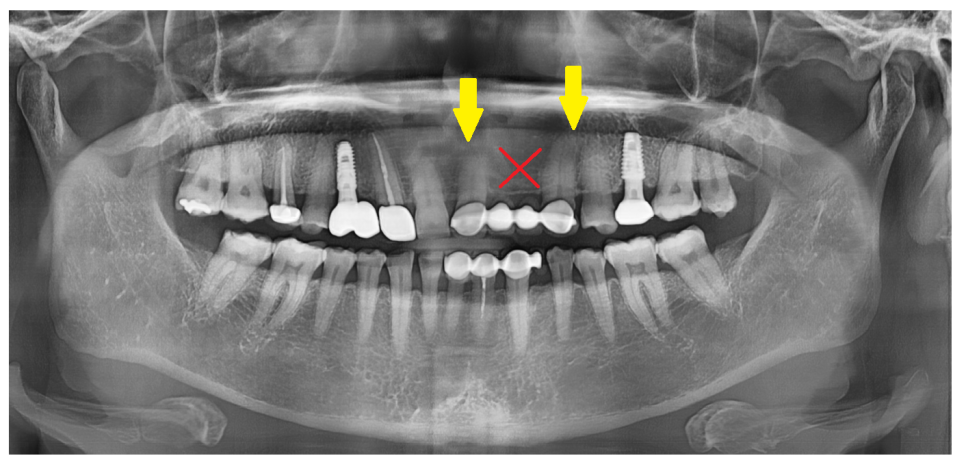

그리고 치아가 상실된지 오래되어

치아가 쓰러져 자리가 부족할 때

임플란트 수술 대안으로 브릿지를 합니다.

위에 환자분도 치아가 빠진지 워낙 오래되어

저 좁은 공간에 치아 3개가 들어가야했습니다.

240408

임플란트는 뼈에 심는건데

공간이 안나오면 브릿지로 대체하죠~